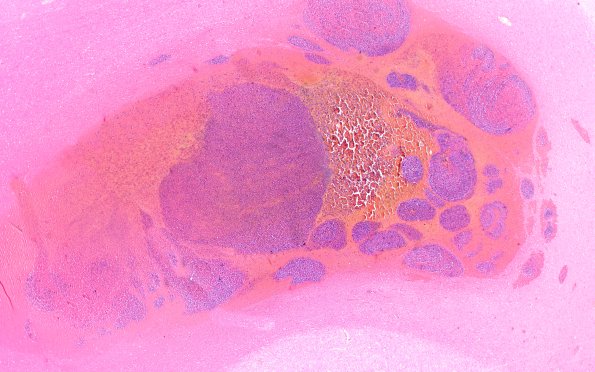

Washington University Experience | NEOPLASMS (HEMATOLYMPHOID) | Granulocytic Sarcoma | 3B2 Leukemic Nodules (Case 3) 2X 1

3B2-5 Higher magnification images of the nodule of image #3B1 demonstrating its myeloblastic center. Surrounding neural tissue showed acute white matter edema with ameboid glia and some karyorrhexis adjacent to the nodules (H&E)